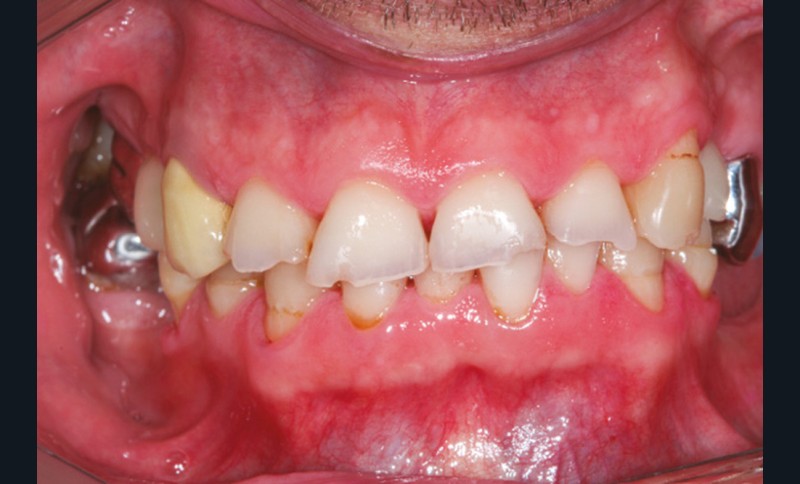

Le principe de protection mutuelle implique que les dents postérieures protègent les antérieures lors de la mastication. Des extractions non compensées de molaires, par exemple, entraîneront une hypersollicitation des antérieures et une usure importante du fait du principe de calage ainsi qu’un risque de perte de dimension verticale (fig. 10 à 13).

La répartition de la charge occlusale sur l’ensemble d’une arcade est aussi perturbée après une ou plusieurs extractions, ce qui peut occasionner des surcharges occlusales pour les dents restantes. Selon le délabrement coronaire de la dent [10], une fracture coronaire amélo-dentinaire ou corono-radiculaire peut intervenir sous cette surcharge occlusale et engager le pronostic de la dent concernée (fig. 14 à 17).